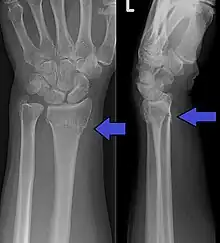

Diagnosis may be evident clinically when the distal radius is deformed, but should be confirmed by X-ray. The differential diagnosis includes scaphoid fractures and wrist dislocations, which can also co-exist with a distal radius fracture. Occasionally, fractures may not be seen on X-rays immediately after the injury. Delayed X-rays, X-ray computed tomography (CT scan), or Magnetic resonance imaging (MRI) can confirm the diagnosis.

Medical imaging

X-ray of the affected wrist is required if a fracture is suspected. Posteroanterior, lateral, and oblique views can be used together to describe the fracture.[5] X-ray of the uninjured wrist should also be taken to determine if any normal anatomic variations exist before surgery.[5]

A CT scan is often performed to further investigate the articular anatomy of the fracture, especially for fracture and displacement within the distal radio-ulnar joint.[5]